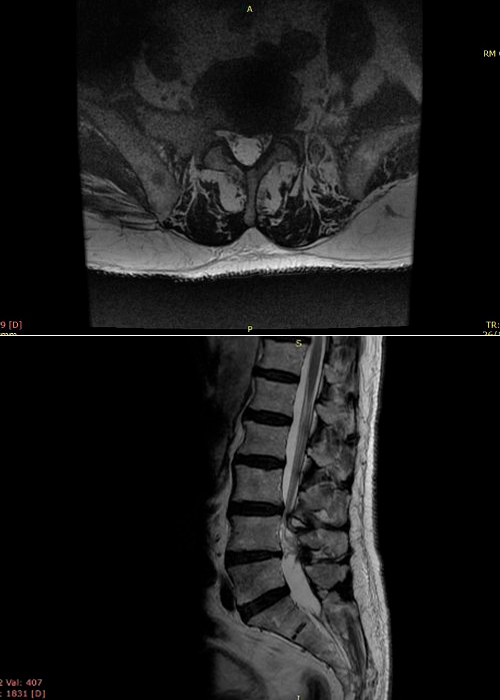

Preoperatorio

Paciente que acude a consulta por estenosis de canal, central con clínica de claudicación neurógena severa a partir de los 50 metros.

El paciente aquejaba de mucho dolor en ambos MMII por igual, reflejos disminuidos tanto aquíleo como rotuliano.

preoperatorio-estenosis-de-canal-instituto-cac